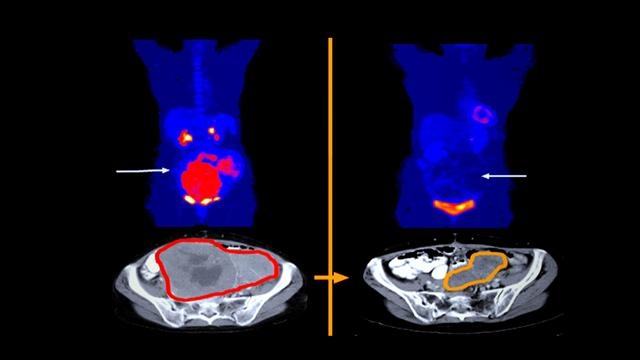

기스트(GIST)는 위장관기질종양을 일컫는다. 병명에서 보듯 식도, 위, 소장, 대장 등 소화기관의 근육층과 복막에 나타나는 종양이다. 하지만 내시경 검사로 찾기가 어렵고 뚜렷한 증상도 없어 다른 병으로 병원에 갔다가 우연히 발견하는 경우가 대부분이다. 한참 진행된 뒤에야 치료하게 되는 것은 이런 이유 때문이다. 기스트는 희귀한 데다 조기 진료가 어려운 종양으로 인식됐지만 표적 치료제의 일종인 ‘이매티닙’으로 치료가 가능하다는 연구가 나와 환자들에게 희망을 주고 있다.

기스트는 외부 점막 조직 검사로 확진을 내릴 수 없어 수술과 동시에 진단이 이뤄져야 한다. 일반적인 암이나 궤양에 비해 증상도 크지 않아 병을 키워 병원에 오는 환자가 많다. 간을 포함한 전신으로 전이가 잘돼 수술도 어려운 상황이 된다. 이때 떠올릴 수 있는 치료제가 이매티닙이다. 이매티닙은 문제가 되는 암세포만을 정확히 골라 공격한다. 기존 항암 치료에 비해 평균 생존 기간도 6배 이상 높고 부작용도 적어 치료를 받으면서 일상생활 하는 것이 가능하다는 장점이 있다.